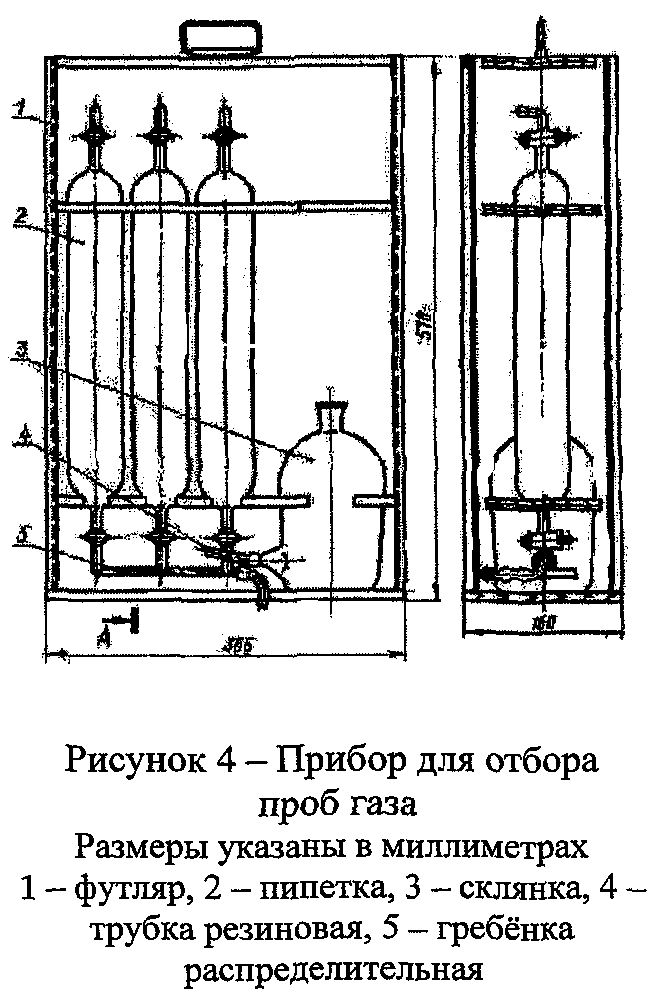

Объём кислорода, пропущенный через поглотительный раствор, измеряют с помощью склянки с тубусом (рис. 3) или прибора для отбора проб газа (рис. 4), присоединенного к короткой трубке склянки (рис. 1 или 2) на выходе газа.